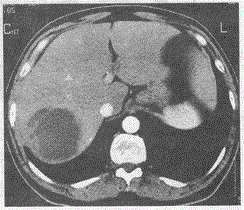

问题 女,45岁,高热7天,伴有上腹部疼痛,增强后如图所示,最可能的诊断是

选项 A.肝癌 B.肝包虫 C.肝脓肿 D.肝囊肿 E.肝血管瘤

答案 C